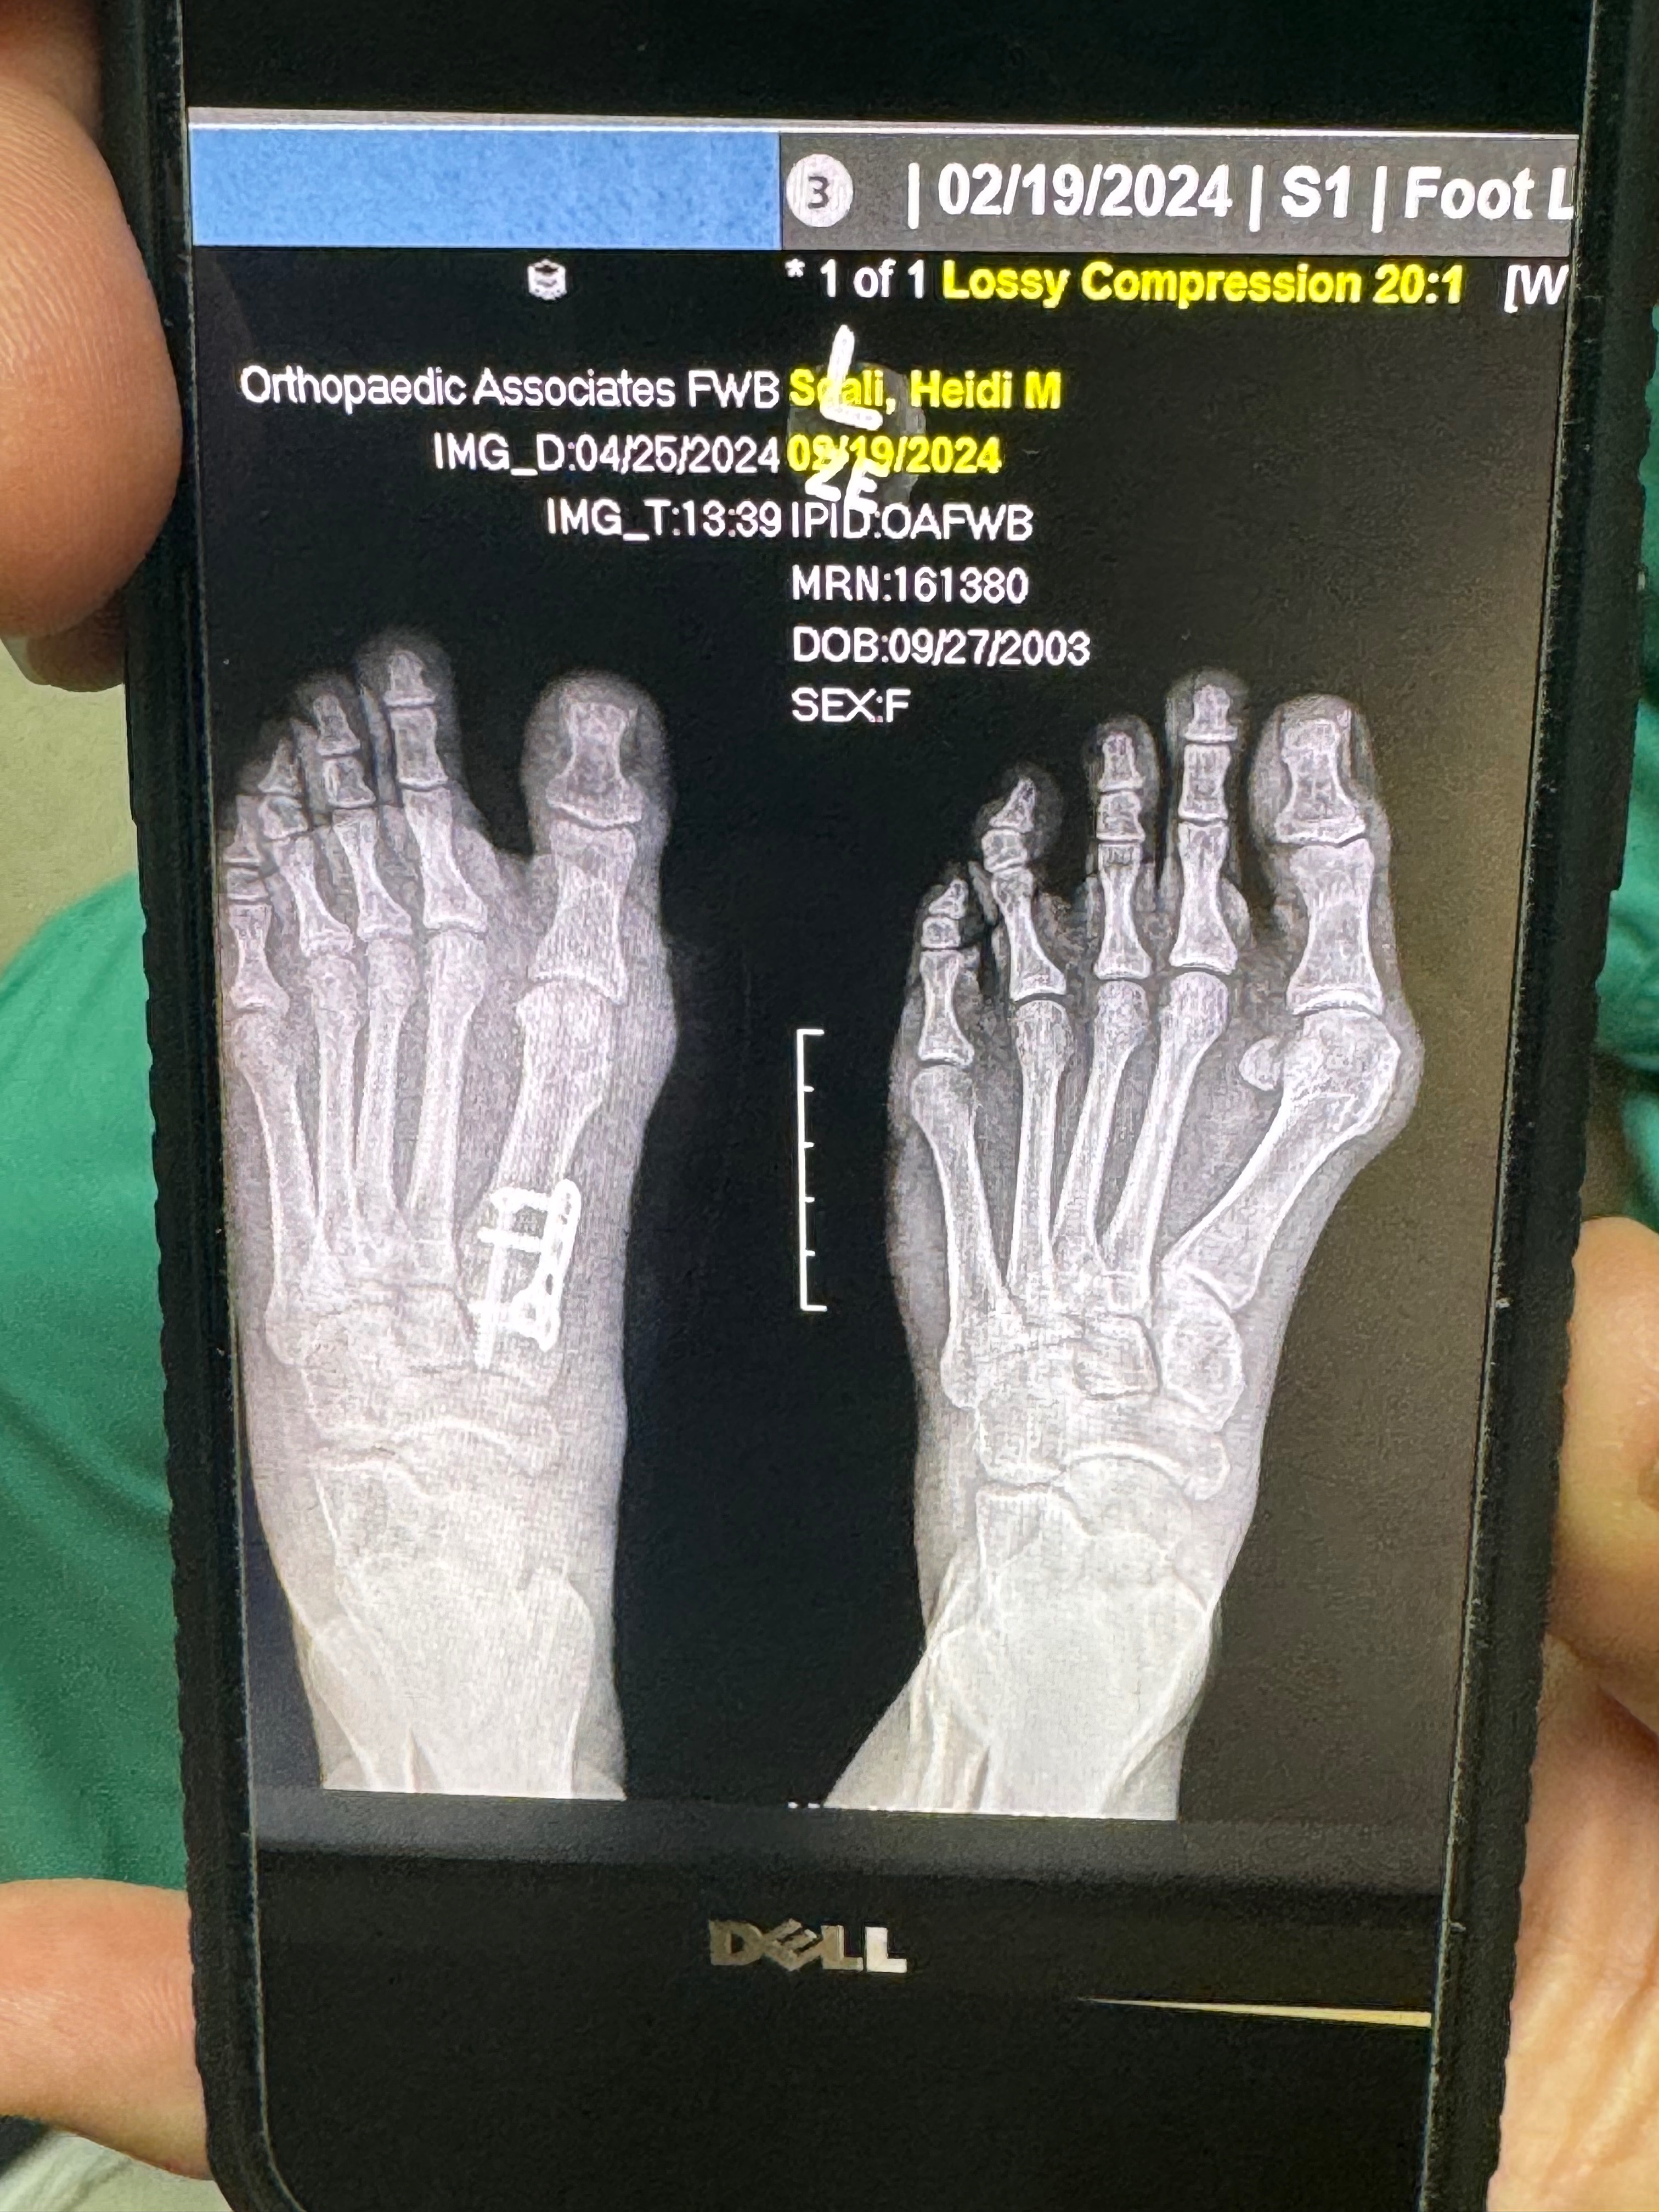

This year has been a fight — one I never expected, but one I am determined to win. I'm currently battling chronic osteomyelitis in my left foot, working hard to avoid amputation. So far, l've undergone four surgeries, with more still ahead, and I go to the doctor daily for IV antibiotics. I'm non-weight bearing for now, and much of my recovery depends on how my body responds to treatment.